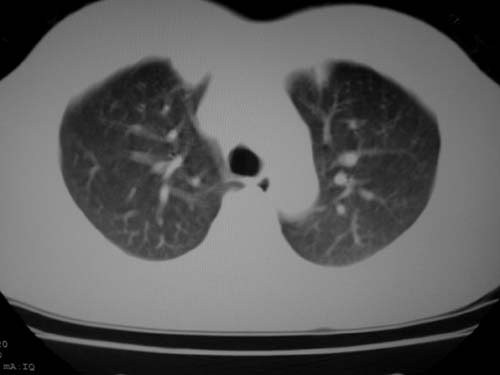

标题: CT19540: 31岁。自述结核性胸水治疗两个月后,在外院拍x线发 [打印本页]

标题: CT19540: 31岁。自述结核性胸水治疗两个月后,在外院拍x线发

右侧胸壁结节状软组织影伴相应肺叶内受侵,伴右侧胸腔积液。考虑:结核性可能大。

1、炎性包块;2、右侧少量胸膜积液。

1、炎性病变,结核可能;2、右侧少量胸膜积液。

病灶也是发生于结核球好发部位,支持结核

考虑结核性结节

多考虑包裹性胸腔识液。

右侧胸壁结节状软组织影伴相应肺叶内受侵,伴右侧胸腔积液,结合临床,首先考虑结核。

考虑结核性胸膜炎,胸膜肥厚,不除外胸膜间皮瘤可能,建议复查。

支持结核,胸膜间皮瘤不排除.

1)考虑右侧结核性胸膜结节。2)右侧胸膜增厚+包裹性胸腔积液。

支持结核性胸膜炎表现

结核性脓胸、肺内结核?